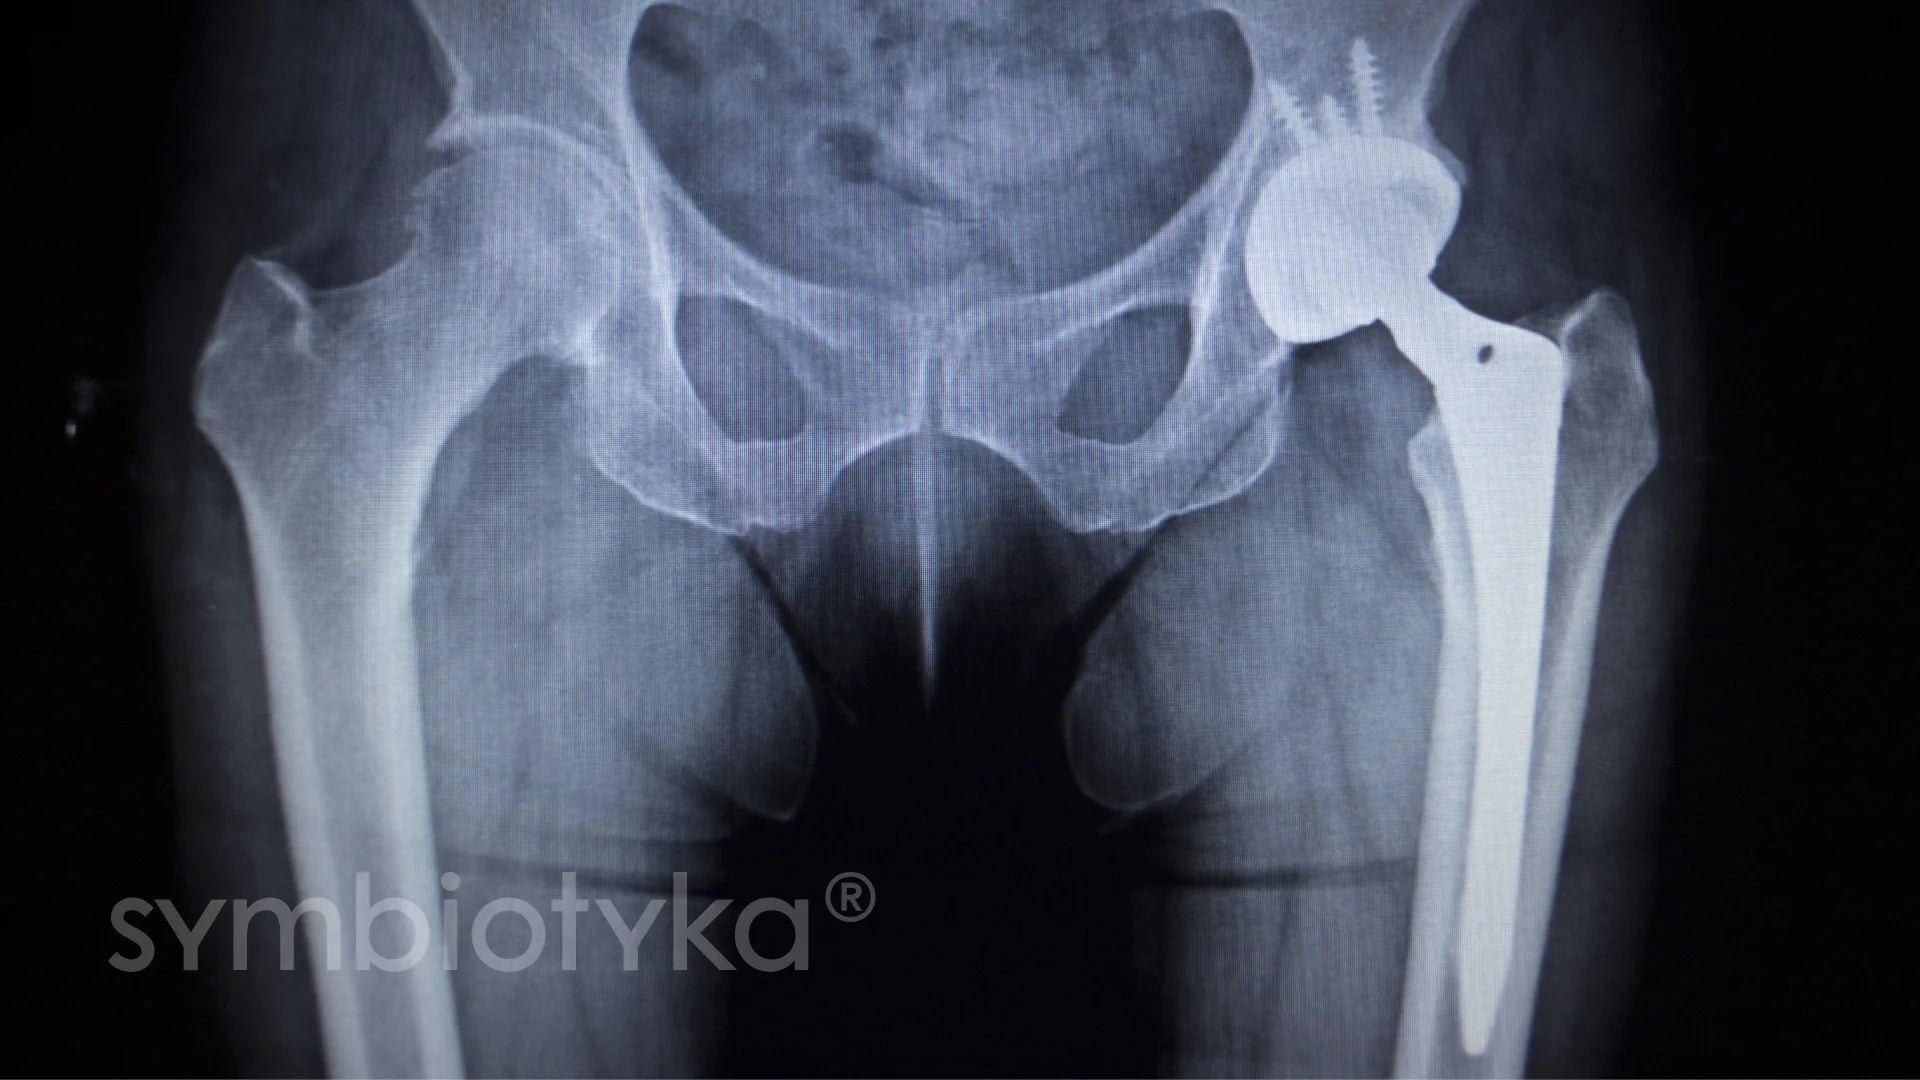

Ендопротезування кульшового суглоба — це хірургічна операція, під час якої зношений або пошкоджений суглоб замінюється штучним імплантом. Мета — усунути біль, повернути рухливість і покращити якість життя пацієнта.

Операція із заміни кульшового суглоба (тотальне ендопротезування) передбачає видалення пошкоджених кісткових і хрящових структур та їх заміну металевими, керамічними або поліетиленовими компонентами.

Процедура добре стандартизована та відпрацьована у світовій ортопедії.